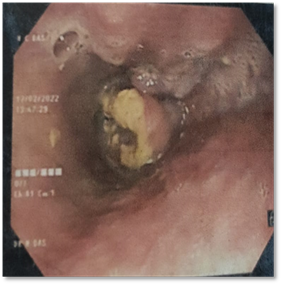

Upper GI-Endoscopy is the gold standard

appears as ulcer-proliferative growth on Upper GI-endoscopy (Figure 6).

Figure

6. Ulcero-proliferative growth at middle

thoracic esophagus on UGI-endoscopy.